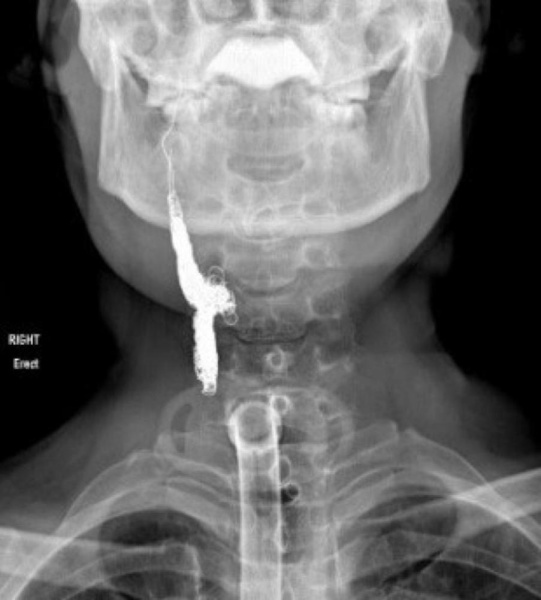

وليد صبري * إجراء 3 عمليات جراحية نوعية ومعقدة* المريض خسر 75% من دمه بعد انفجار الشريان السباتي* الفريق الطبي أجرى قسطرة عاجلة لسد النزيف من الشريان* المريض تعافى تماماً دون مضاعفات أو عودة الورم السرطانيكشف استشاري جراحة الأنف والأذن والحنجرة والمتخصص في جراحة الأذن وجراحة الرأس والعنق بمستشفى الملك حمد الجامعي د. عمر صبرا عن "تمكن فريق طبي كبير ومختص في مستشفى الملك حمد الجامعي من إنقاذ حياة مريض في العقد الخامس من العمر كان يعاني من سرطان الحنجرة، عبر إجراء 3 عمليات جراحية معقدة ونوعية".وأضاف في تصريحات خاصة لـ"الوطن"، "تم علاج المريض بالعلاج الكيماوي والإشعاعي منذ عدة أعوام في إحدى المستشفيات، وقد تلقى العلاج المناسب الذي كان من المفترض أن يخضع له، وبعد سنتين، حدثت انتكاسة للمريض، حيث يوجب في تلك الحالات استئصال الحنجرة وتنظيف الغدد الليمفاوية بالعنق".وقال د. صبرا "قام الفريق الطبي المختص باستئصال الحنجرة والغدد الليمفاوية بـ "تجريف الرقبة"، "وهو الاسم التقني للعملية"، ومن بعد العملية بشهر، وبعد التأكد من التئام الانسجة، وتناول المريض للطعام من الفم بشكل طبيعي، عاود المريض الرجوع إلى المستشفى نتيجة معاناته من مضاعفات لمثل تلك الحالات، حيث انفجر الشريان السباتي الذي يتوجه للمخ، فيما تعد تلك المضاعفات من المضاعفات النادرة جداً التي تودي بحياة المريض في الكثير من الحالات، بعد جراحات تتلو العلاج بالأشعة، لأنه ثبت علمياً أنه عند إجراء جراحة بعد خضوع المريض للعلاج الكيماوي والإشعاعي تكون الأنسجة ضعيفة جداً، والالتئام يكون ضعيفاً، وبالتالي بدأت الأنسجة تتفتح وحدث انفجار للشريان، وخسر المريض تقريباً نحو 75% من دمه خلال ساعات قليلة جداً".ونوه إلى أن "المريض خضع لنحو 3 عمليات جراحية نوعية، الأولى، كانت جراحة علاجية لاستئصال الحنجرة وتجريف الرقبة، وقد قمت بها، والعملية الثانية، كانت إغلاق نزيف الشريان المنفجر، حيث أدى إلى خسارة نحو 75 % من دمه، وقد أجراها استشاري الأشعة د. وائل إبراهيم، والعملية الثالثة، قمت بإجرائها مع جراح زائر من الخارج يدعى د. مؤمن البشير، حيث قمنا باستئصال منطقة الجلد الملتهبة، وقمنا بترميم الرقبة، حيث تعافى بشكل كامل دون أية مضاعفات أو دون عودة الورم السرطاني مرة أخرى".من جانبه، كشف استشاري الأشعة التداخلية في مستشفى الملك حمد الجامعي، د. وائل إبراهيم، في تصريحات خاصة لـ"الوطن" أن "المريض كان يعاني من نزيف حاد في الشريان السباتي بالرقبة، ما أدى إلى حدوث نزيف حاد في الأنف والفم، وعلى إثر وصول المريض إلى المستشفى، تبين استحالة السيطرة على النزيف بالطرق الطبيعية والعادية فتم نقل المريض إلى قسم الأشعة التداخلية حيث قام الفريق الطبي بعمل قسطرة عاجلة لسد النزيف من الشريان حيث تمت السيطرة على النزيف بالكامل، وقد استغرقت الجراحة نحو ساعة".

* إجراء 3 عمليات جراحية نوعية ومعقدة * المريض خسر 75% من دمه بعد انفجار الشريان السباتي * الفريق الطبي أجرى قسطرة عاجلة لسد النزيف من الشريان * المريض تعافى تماماً دون مضاعفات أو عودة الورم السرطاني